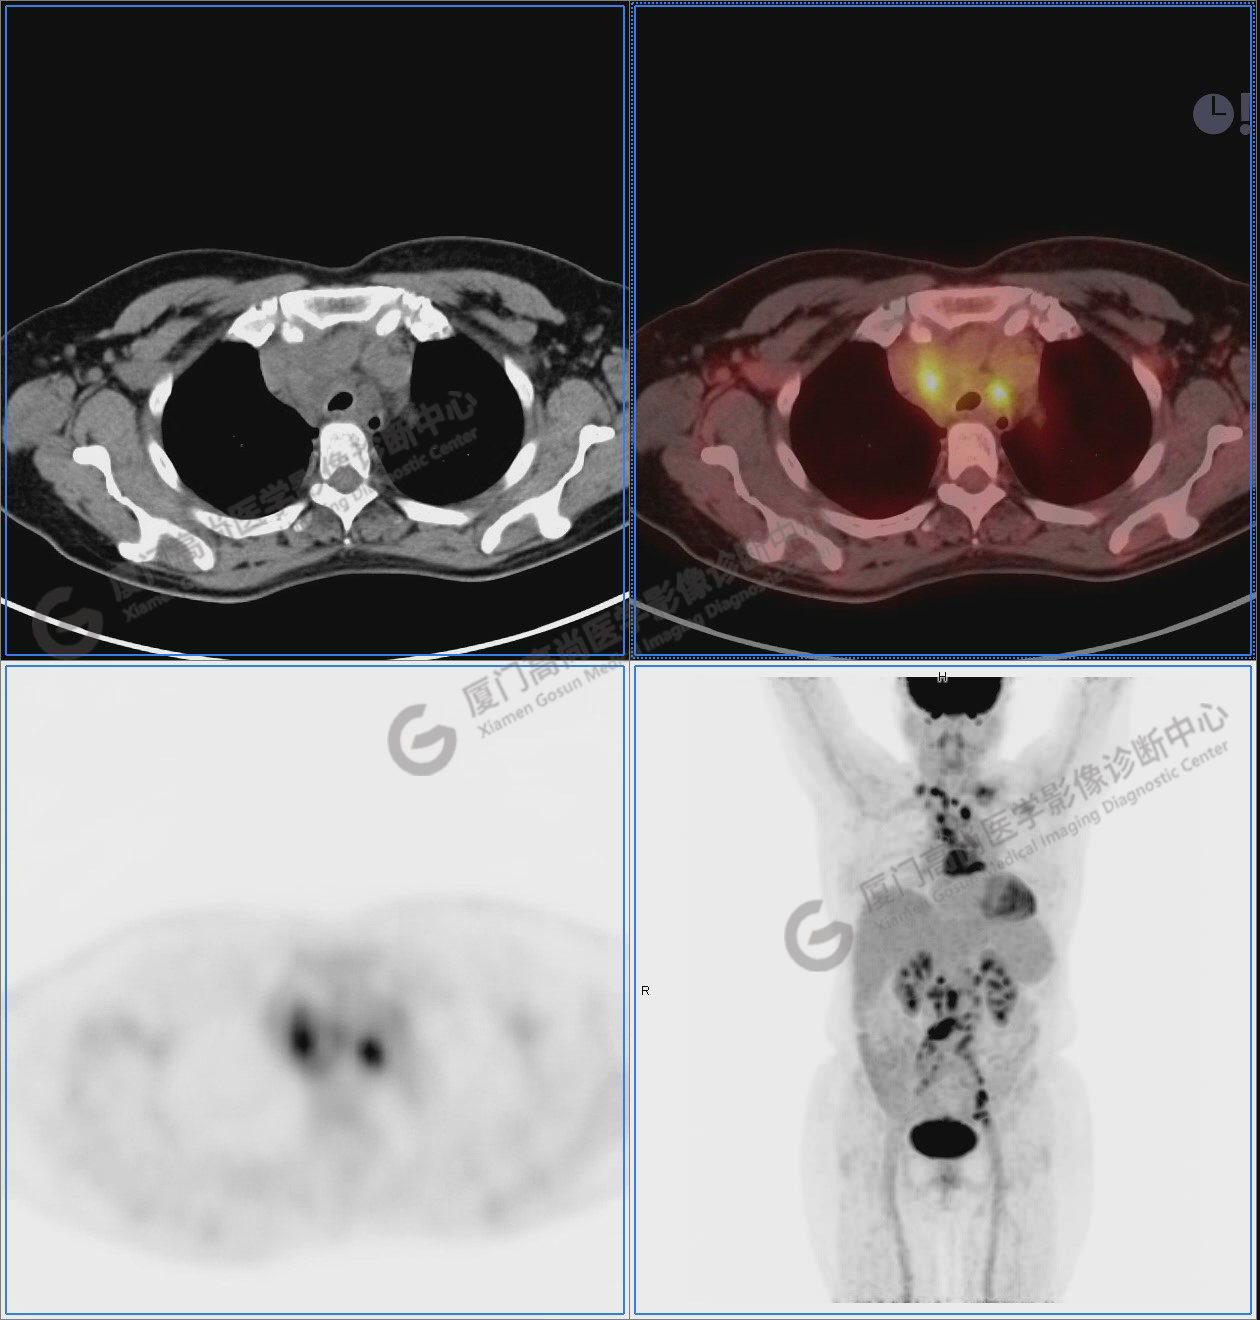

圖1:PET/CT全身圖像

圖2-9:雙側(cè)鎖骨區(qū)、縱隔、右側(cè)內(nèi)乳區(qū)、腸系膜緣、腹膜后、雙側(cè)髂血管旁及盆腔多發(fā)腫大淋巴結(jié)影,代謝不同程度增高,考慮為轉(zhuǎn)移。